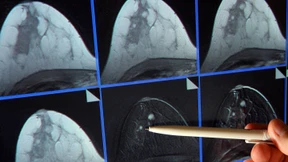

Auf dem weltgrößten Krebskongress in Chicago hebt eine deutsche Studie alte OP-Regeln aus den Angeln: Schont die Lymphknoten ist ihr Fazit. Ein Paradigmenwechsel bahnt sich an.